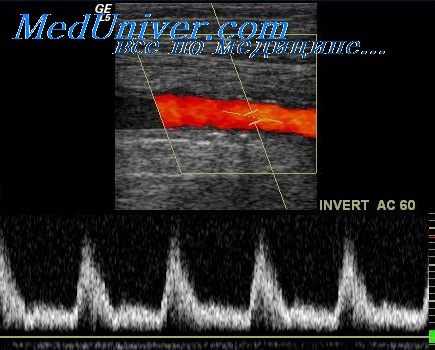

Для иллюстрации исследования ауторегуляции мозгового кровообращения с помощью теста Гиллера на рисунке показаны этапы проведения этой пробы под контролем цветного дуплексного сканирования.

Из рисунка видно, что в покое TAMXQ (V0) была 51 см/с, после декомпрессии ТАМХ, (V,) первых двух посткомпрессионных циклов равнялась 67 см/с, а время восстановления линейной скорости кровотока составляло почти 8 с. По формулам рассчитали требуемые индексы, значения которых оказались: КО - 1,31, САР -3,88%с-1. с учетом того, что возраст испытуемого составлял 47 лет, согласно таблице показатели находятся в границах нормы, следовательно, ауторегуляция в данном случае сохранена.